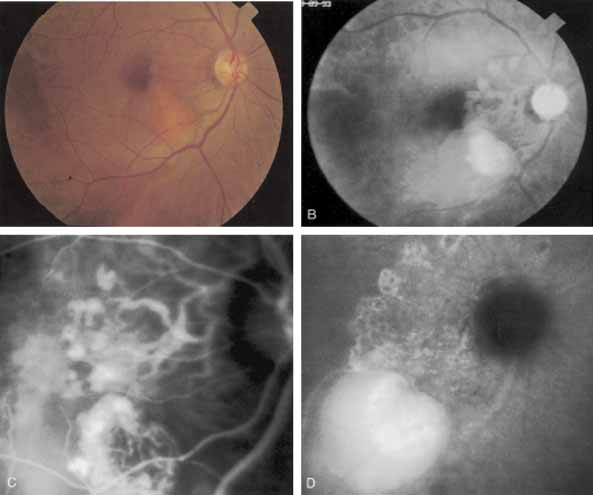

Idiopathic polypoidal choroidal vasculopathy, also known as posterior uveal bleeding syndrome, typically affects darkly pigmented persons who exhibit acute exudative manifestations in the posterior pole, including subretinal hemorrhage and, occasionally, CNV.76,77 ICG angiography facilitates a more definitive diagnosis than fluorescein angiography because it achieves a sharper image of the primary lesion,51,77,78 dilated choroidal vessels terminating in polypoidal or aneurysmal excrescences at the level of the choroid (Fig. 23). These vascular changes account for the secondary exudative and hemorrhagic detachments of the retinal pigment epithelium and neurosensory retina that are characteristic of this disorder. Furthermore, ICG angiography may provide a better means of differentiating the relatively benign aneurysm-like changes at the level of the larger choroidal vessels from CNV, a more devastating secondary manifestation of this chronic disease.79

Fig. 23 A. Clinical photograph of a patient with idiopathic polypoidal choroidal vasculopathy demonstrating the branching lesion at the level of the choroid. There is a more nodular elevation in the inferior macula. A hemorrhagic detachment of the retina is noted temporally in a curvilinear fashion. B. “Green-free” photograph that more vividly demonstrates the branching vascular pattern of this condition. C. High-magnification image of an early-phase indocyanine green (ICG) study reveals filling of the vascular channels at the level of the choroid leading to the polypoidal lesions. Note that the inferior, more elevated lesion, which is nodular on clinical examination, consists of an internal network of branching vessels. D. Late-phase ICG study demonstrates ring-like staining of the small polypoidal lesions. The larger lesion shows intense but nonhomogeneous staining.